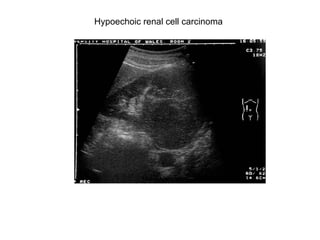

Hypoechoic renal cell carcinoma